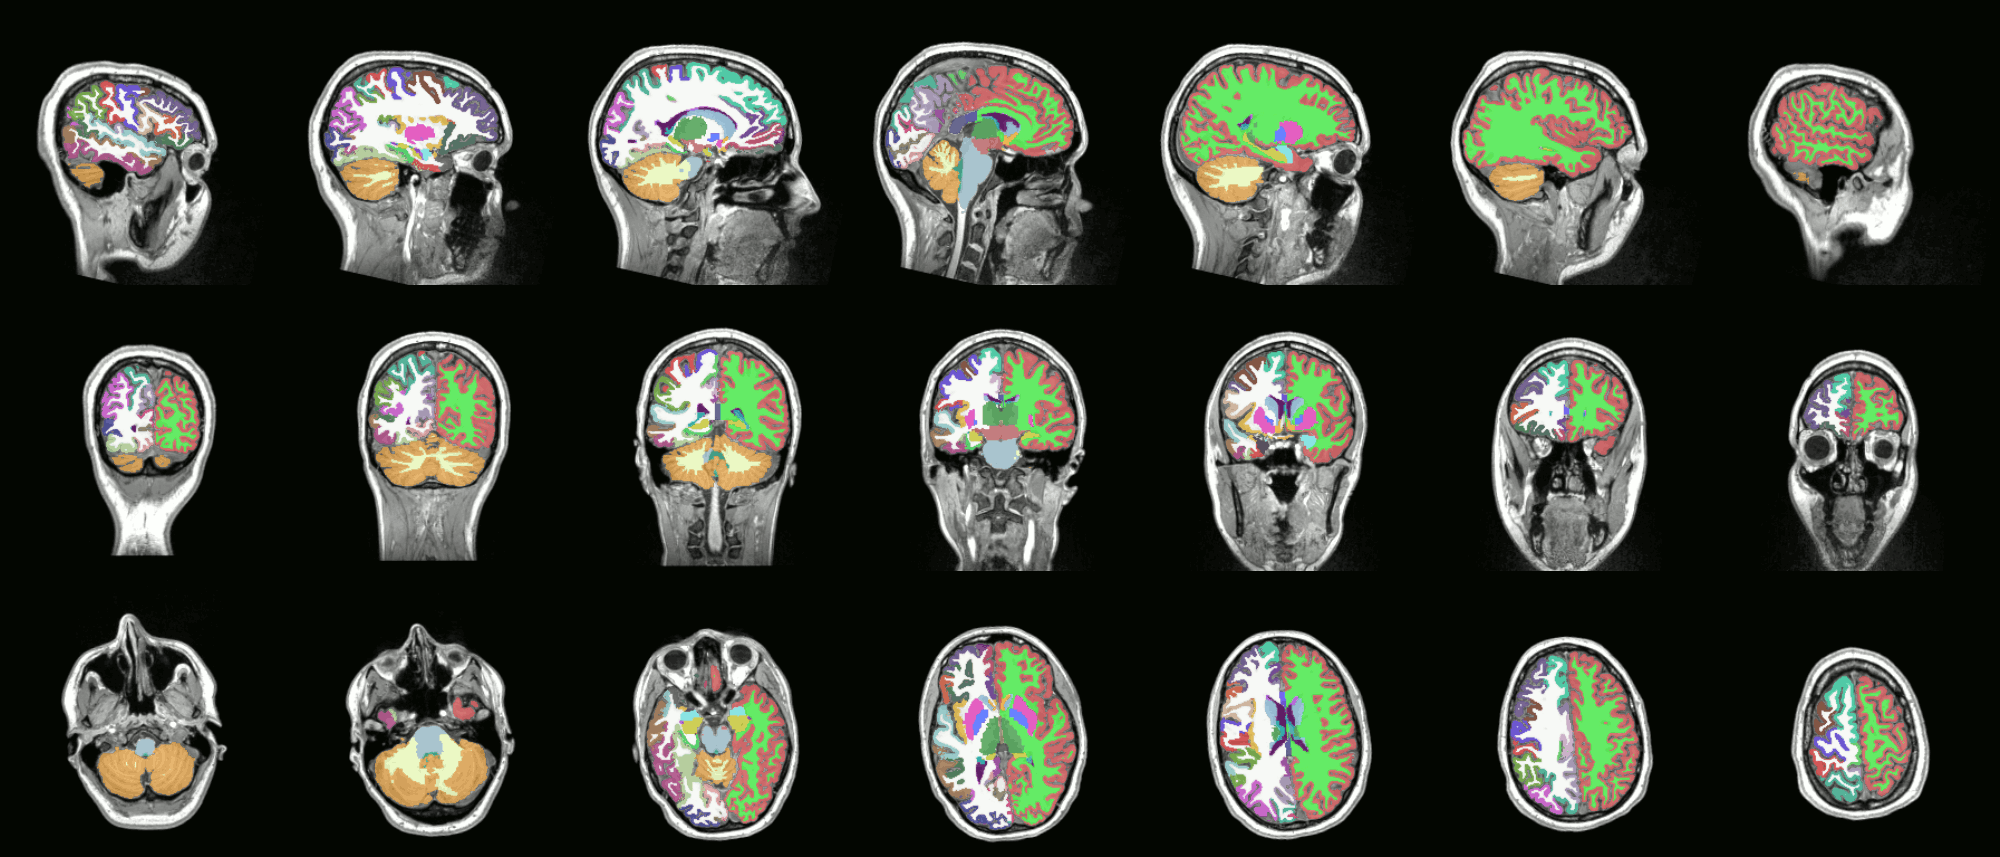

Analyses

Quality Assessment

- One task - one QA

- General summary

- Global information

- Visual output

- Easy interface web-based